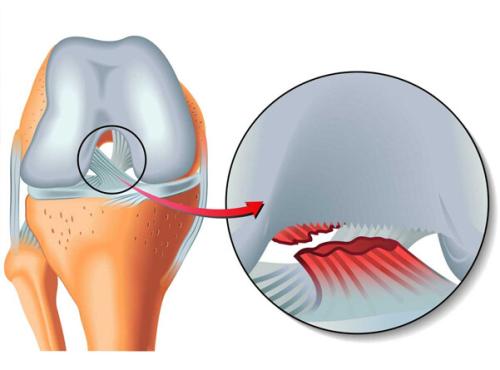

Patella (Diz kapağı) Çıkığı 1646 OkunmaMenisküsler nasıl yırtılır?

Menisküs yırtığı diz ekleminde meydana gelir. Bu yırtık ayak sabitken ani bir dizden dönme hareketi, yüksekten düşme veya dizin üzerine aşırı bir k...

Menisküs 120 OkunmaMenisküs yaralanmalarında PRP

Gerek akademik dünyada gerekse de hastalar tarafında PRP’nin menisküs iyileşmesine etkili olacağı umudu artarak devam etmektedir. Tüm belirs...